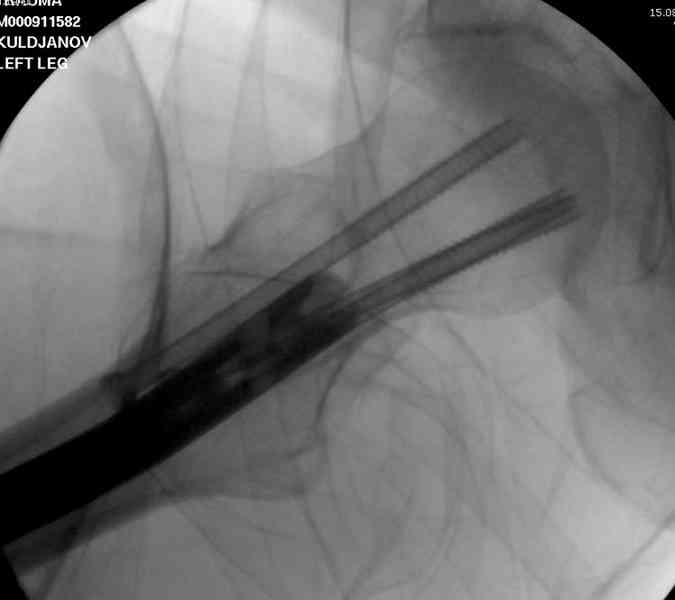

В первый же день произведено антеградное штифтованием DePuy Trochanteric Nail.

На второй день (7) обнаружен пропущенный перелом,

сделаны Компьютерная Томограмма

и проведены шурурпы через и спереди штифта без удаления.